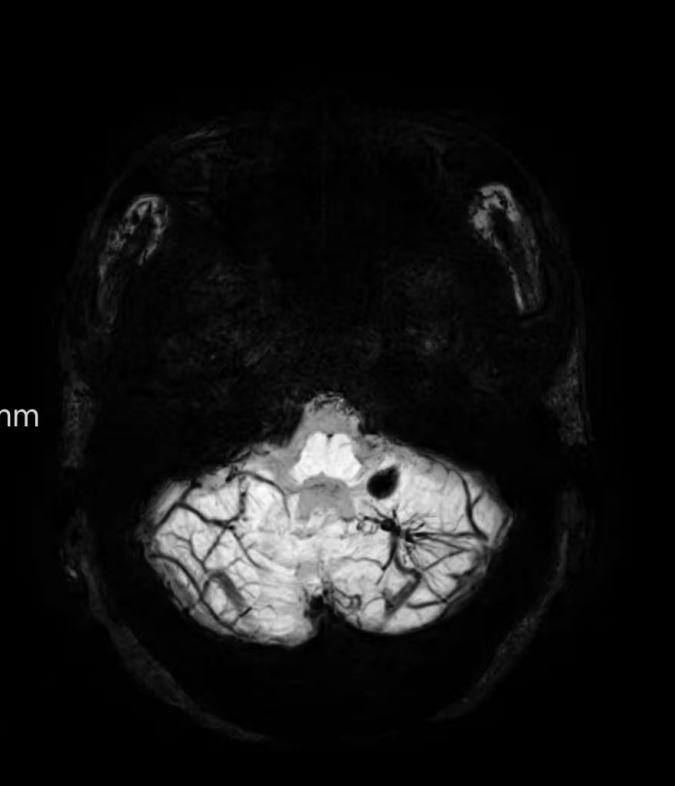

臨床中遇到一位患者,中年女性,反復出現頭痛,時輕時重,常規CT及磁共振檢查無明顯異常發現,最后建議加做一個磁共振磁敏感加權成像(SWI),結果發現是左側小腦發育性靜脈畸形(DVA),SWI清晰顯示畸形的靜脈及周圍含鐵血黃素沉積;如下圖。這正是她頭痛的原因。

①診斷靜脈畸形:SWI能高精度地顯示發育性靜脈畸形——一種常見的腦血管畸形。在SWI上,發育性靜脈畸形會呈現典型的“海蛇頭”或“水母頭”征,即一堆細小的髓靜脈匯入一支粗大的引流靜脈。